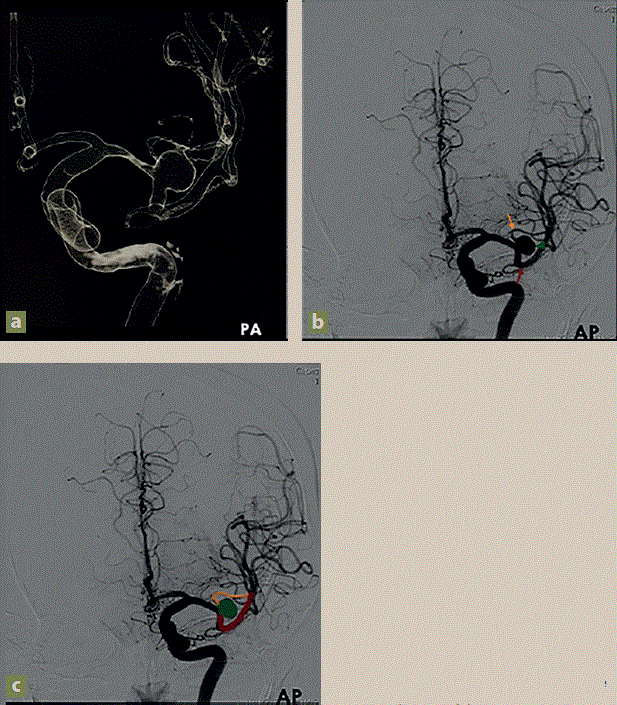

Figura 1 Aneurisma sacular en la bifurcación de la ACMI. a) 3D angiografía diagnóstica (AxDx) en posición posteroanterior, b) y c) AxDx eje carotídeo izquierdo, proyección AP, aneurisma sacular (cabeza de flecha/verde), rama dorsal dela ACMI (flecha naranja) con origen en pared lateral del aneurisma, rama ventral de la ACMI (flecha roja)

Se realizó una cateterización del eje carotideo izquierdo hasta segmento C2 vertical utilizando la guía. Posteriormente, se procedió a ascender con el catéter diagnóstico Simmons. Se llevaron a cabo adquisiciones ortogonales en las proyecciones AP Towne, lateral y oblicua, con el fin de evaluar el trayecto extra e intracraneal. Se destacó una imagen aneurismática en la bifurcación de la arteria cerebral media izquierda (ACMI), donde se adquirió una imagen en 3D. Las medidas obtenidas del aneurisma fueron: 6.7 × 7.3 mm en sus diámetros, con un cuello de 3.6 mm. Se observó una rama emergente del domo aneurismático. Además, el trayecto de las estructuras arteriales y venosas intracraneales del sistema carotídeo izquierdo se encontró preservado (figura 2).